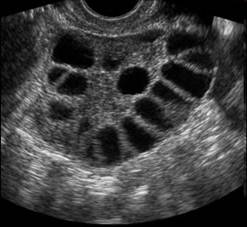

Nella fase follicolare precoce l’ovaio è ormonalmente poco attivo. Per tale motivo i livelli sierici di estrogeni e progesterone in questo periodo risultano bassi. Il GnRH stimola la secrezione dell’FSH, necessario per il reclutamento dei follicoli antrali dal pool di follicoli primordiali, da cui verrà selezionato quello che diverrà il follicolo dominante e andrà incontro ad ovulazione. L’ovaio in questa fase è quiescente, possono evidenziarsi piccoli follicoli fra i 3-8 mm di diametro e solo occasionalmente è possibile riscontrare il corpo luteo del ciclo precedente. Nei primi giorni della fase follicolare precoce l’endometrio è ecograficamente difficilmente riconoscibile, una volta terminata la mestruazione si visualizza come linea sottile.

Ecograficamente, entro 7 giorni dall’inizio del ciclo mestruale è possibile evidenziare la presenza di follicoli con diametro di 9-10 mm. L’incremento dei livelli sierici di estradiolo determina la proliferazione delle ghiandole endometriali con lo sviluppo di un pattern a triplo strato (epitelio proliferativo o estrogenico).

In questa fase a livello ovarico viene isolato il follicolo dominante ed i restanti follicoli che facevano parte della coorte selezionata all’inizio del ciclo mestruale vanno incontro ad atresia. Il follicolo dominante aumenta il proprio diametro di circa 2 mm al giorno fino a raggiungere i 20-26 mm che indicano la piena maturazione. L’aumento dei livelli di estradiolo determina un incremento dello spessore endometriale e della viscosità del muco cervicale.

Si ha sviluppo dell’utero e delle ovaie, con aumento del numero di follicoli. Nel soggetto prepubere l’utero è a forma di goccia e il rapporto collo/corpo (diametro antero-posteriore) è 35 mm e compare la linea iperecogena centrale (linea endometriale). All’inizio della pubertà il volume ovarico è 1.3 cm3 e al menarca di circa 4 cm3.